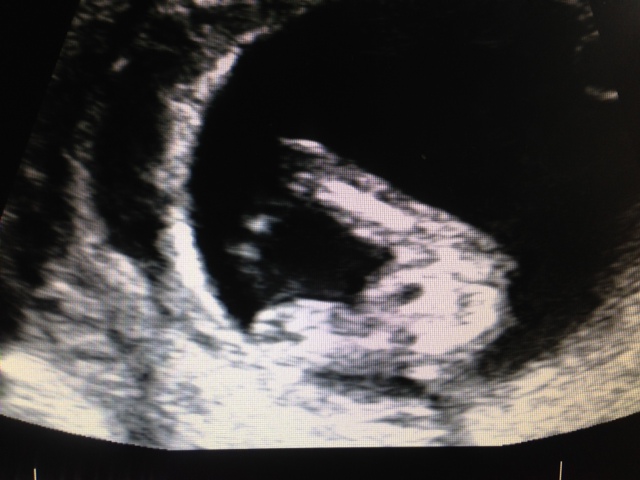

These are my pics from my scan at 12+3. I'm not really sure if you can see anything but I would love to hear your opinions.

I'm not seeing any clues.

Not clear at all but I'm gonna guess girl.